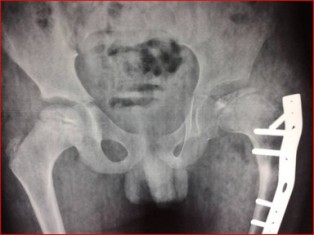

Diagnosing Perthes Disease involves a combination of clinical evaluation, medical history assessment, and imaging studies. X-rays and MRI scans are commonly used to confirm the diagnosis and determine the extent of bone damage.

• If the femoral head lesions progress, surgery may be required to preserve hip joint congruity.

• Procedure: The hip bone is cut and realigned, and a plate is applied to hold the bone in place.

• Outcome: When performed at the right time, long-term results are excellent. However, delayed treatment may lead to hip deformity and pain in adulthood.